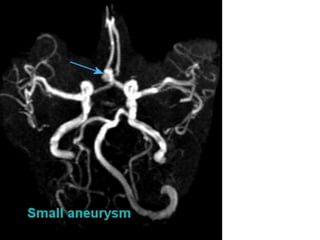

3D TOF is now accepted as a non-invasive screening tool for

familial aneurysmal disease.

Sensitivity is greater for detecting aneurysms > 3mm (94%) than

aneurysms < 3mm (38%). ( White et al 2000)

Overall inferior to DSA and misses aneurysm <3mm.(Adams et al

2000)

3D CE MRA is superior to TOF MRA .It is method of choice for

evaluation of giant cerebral aneurysms.

CE MRA shows promise in the follow-up of treated intracranial

aneurysms.

Aneurysms

Multiple aneurysms in a 54-year-old woman.

Multiple aneurysms ina 54-year-old woman.